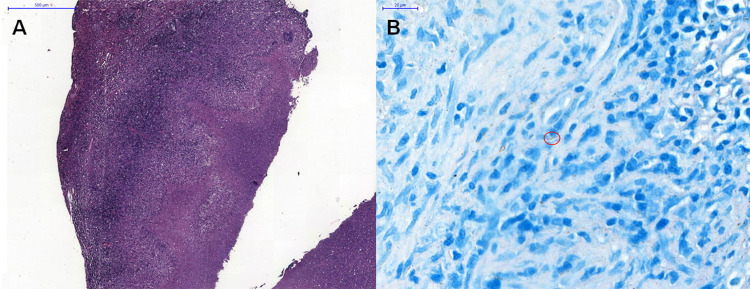

Behçet's disease (BD) is a chronic and multisystem disorder characterized by recurrent oral and genital ulcers, along with ocular, cutaneous, vascular, gastrointestinal, and neurologic manifestations. The etiology is thought to involve an autoimmune response triggered by infectious or environmental factors in genetically predisposed individuals. Mycobacterium tuberculosis has been proposed as a potential trigger for BD, although this association remains rarely reported. We show a compelling case of a patient with BD diagnostic criteria who subsequently developed mediastinal tuberculous lymphadenitis, which was initially suspected as disease activity. This case underscores the importance of considering tuberculosis in BD patients with new or worsening symptoms despite appropriate therapy.